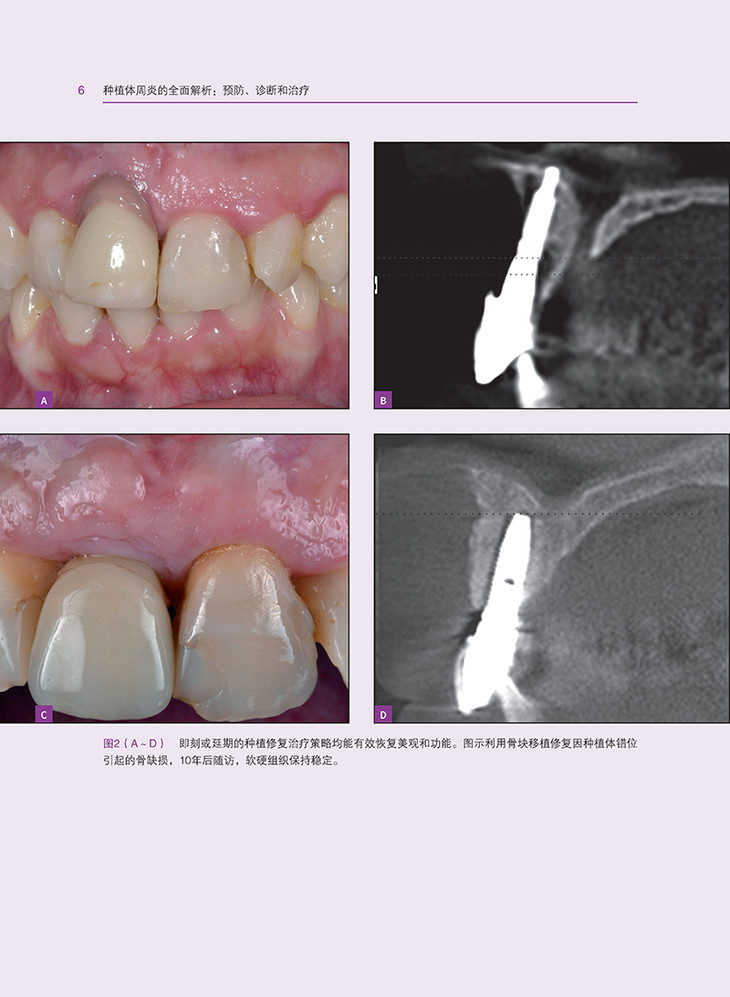

种植体周炎的发生和发展相关问题,从诊断与监测到治疗策略,涵盖了种植体周炎的各个方面。首先,深入探讨了种植体周炎的形态学和表型特征,为读者提供了清晰的认识基础。接着,详细分析了种植体周炎的理想三维软组织和硬组织量,以及影响种植体周炎的局部风险因素、全身因素和不良习惯。同时,本书还介绍了遗传学和表观遗传学对种植体周炎的影响,为深入理解种植体周炎的发病机理提供了新的视角。

在治疗方面,本书从初级预防和次级预防两个层面出发,详细阐述了种植体周炎的预防策略。同时,结合牙周炎治疗的经验,提出了种植体周炎的管理策略,包括非手术治疗、药物联合治疗和手术治疗等。此外,本书还介绍了种植体表面去污策略,以及手术治疗的时机选择,为读者提供了实用的治疗建议。

在再生性治疗和软组织整塑方面,本书提出了EP-DDS原则,为种植体周炎的治疗提供了新的见解。同时,还介绍了生物制剂在种植体周炎治疗中的应用,包括基本原理和疗效评估,为临床治疗提供了有力的支持。